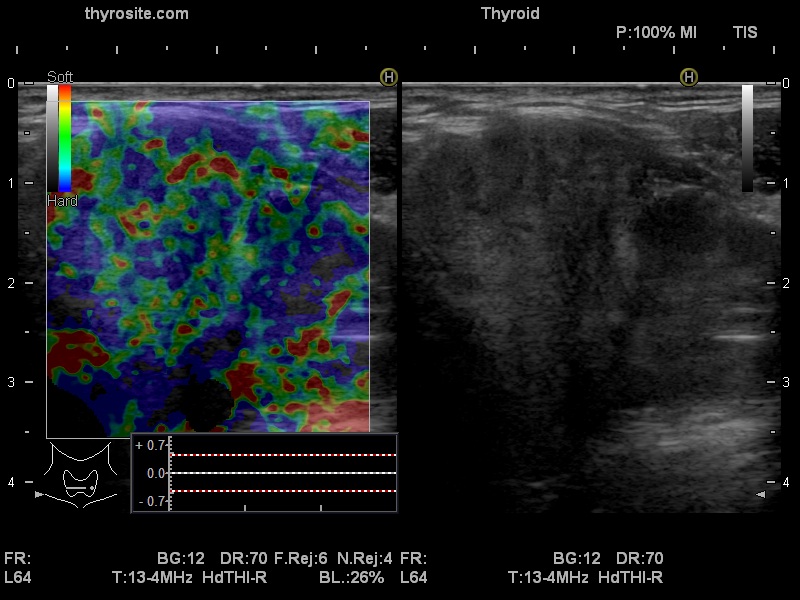

Ultrasonography. The right lobe was echonormal and intact. A large mass occupied almost the entire left lobe. On this side, normal thyroid tissue could only be identified in the dorsal part. The mass was composed of echonormal and hypoechoic areas, had macrocalcifications, irregular intranodular vascularity and proved to be very hard on elastography. There were multiple lymph nodes in III, IV and V left neck compartments. One of the nodes was in close proximity to the jugular vein and was suspicious of having broken into the vessel. The trachea was significantly narrowed at the lower level of the thyroid.

2. There are several remarkable findings in this case, e.g., the destruction of the left lobe by the tumor, the elastography pattern, the relation of the largest metastatic lymph node and the jugular vein, the ultrasound demonstration of the trachea' stricture.